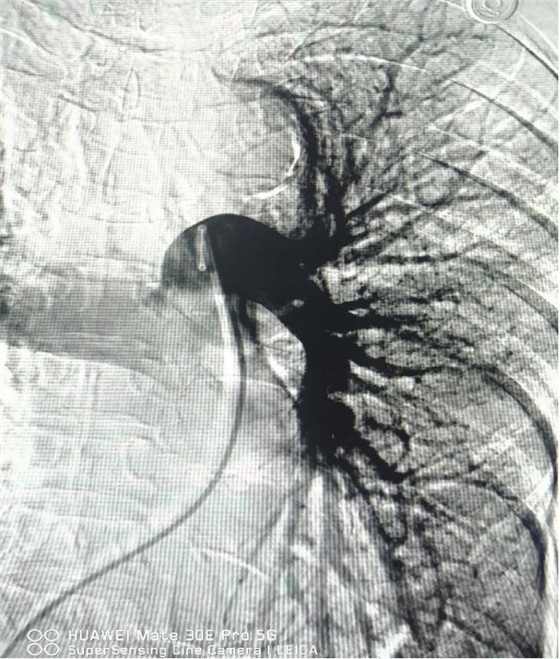

經(jīng)皮肺動脈造影

經(jīng)綜合評估并與家屬充分溝通后,局麻下行肺動脈造影,提示左肺動脈主干及左肺下葉動脈閉塞,立即予以經(jīng)皮肺動脈栓塞導(dǎo)管介入碎栓溶栓術(shù)。在心內(nèi)科韋鋒主任、郭良玉主治醫(yī)師及成婷護(hù)師的默契配合下,爭分奪秒順利完成手術(shù)。術(shù)后即刻復(fù)查肺動脈造影示左肺動脈主干及左肺下葉動脈恢復(fù)血流,生命體征穩(wěn)定,指脈氧恢復(fù)至100%。經(jīng)過精心治療與護(hù)理,目前患者已康復(fù)出院。